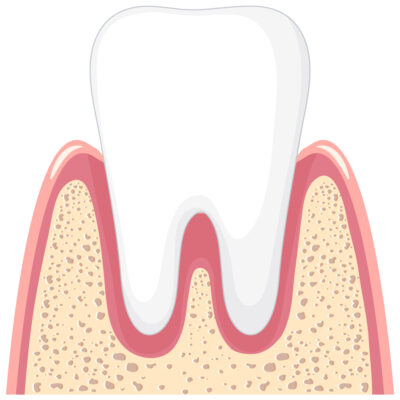

Parodoncia

Cuando nuestras encías padecen enfermedades inflamatorias generadas por acumulación de sarro o sangrado de encias como gingivitis pueden avanzar y afectar el soporte de tus dientes si no son tratados a tiempo aflojandolos y pudiendose perder.

La parodoncia es el área de a odontología encargada de devolverte esa salud en tus encias, devolviendole a tus dientes la fijación nuevamente para que puedas libremente volver a masticar con toda la confianza.

También entre otras muchas cosas pueden mejorar y fortalecer tus encías a través de muchos tratamientos oportunos para que siempre tengas una salud bucal apropiada.